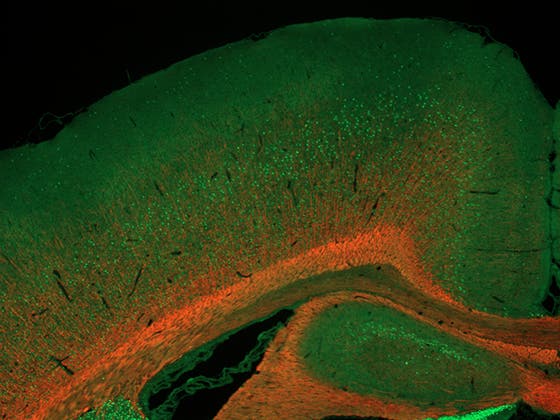

Will MSC treatment boost myelination (red, MBP) in brains of rats exposed to fetal growth restriction as a model for encephalopathy of prematurity? Deep cortical layers are stained for CTIP2 (green). Courtesy of Judit Alhama Riba.